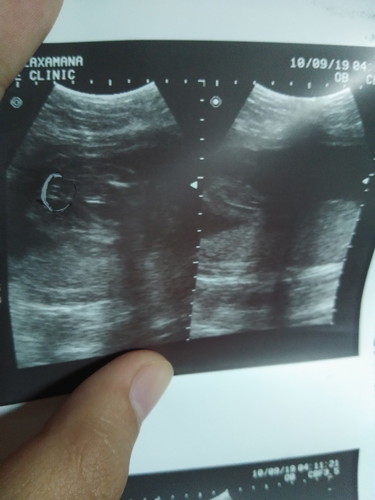

Momsh ano sa palagay nyo? Baby girl or boy?

girl momsh. Humberger sign 😁

gurl po yan momshie